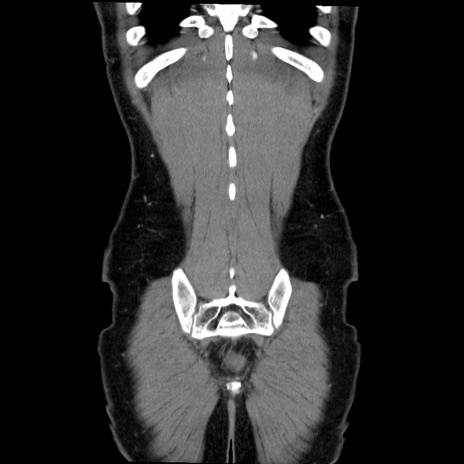

症例36(冠状断像)

【症例】20歳代 男性

【主訴】心窩部痛

【現病歴】今朝より上腹部痛あり。一旦軽快していたが再度出現したため救急要請。昨日夕に白身の魚を含む刺身を食べた。

【身体所見】BP 136/89mmHg、HR 74/min、BT 37.0℃、腹部:膨満、軟、心窩部に圧痛あり。反跳痛なし、筋性防御なし、腸雑音やや亢進あり。

【データ】WBC 17700、CRP 0.48